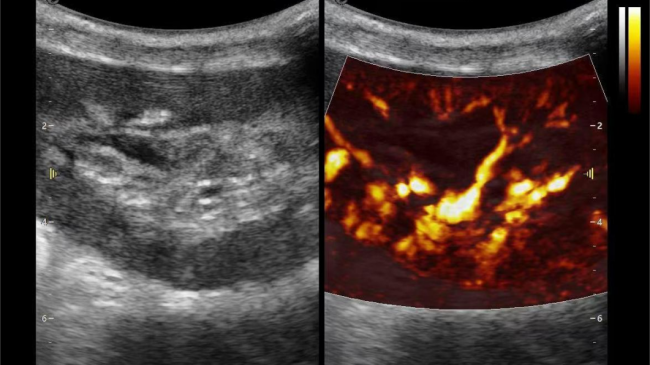

开启肾移植微观视界 | 银河官网黑科技为您“移”路护航(图7)

微米级超高分辨率血流信号显像

开启肾移植微观视界 | 银河官网黑科技为您“移”路护航(图8)

肾脏的灌注评估,RI/VI量化数据

开启肾移植微观视界 | 银河官网黑科技为您“移”路护航(图9)

开启肾移植微观视界 | 银河官网黑科技为您“移”路护航(图10)

开启肾移植微观视界 | 银河官网黑科技为您“移”路护航(图11)

超微视血流显像评估肾移植术后灌注情况

这一项无创、无辐射操作简便且无需造影剂的黑科技,相当于用"高速摄像机"记录血液细胞的运动轨迹,让血管并发症"无处遁形。